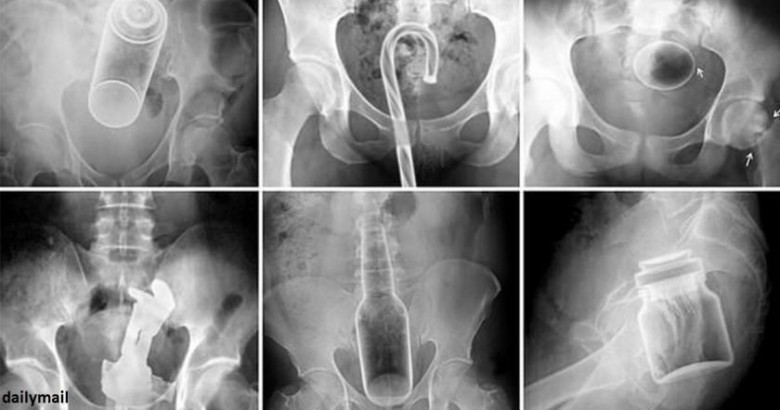

10 տարօրինակ առարկա, որ հայտնվել են մարդկանց օրգանիզմում. հետաքրքիրն այն է, թե ինչպես է դա պատահել (Photo)

Դանակ, պատառաքաղ, մանկական խաղալիքներ ու գարեջրի շշեր: Այս ամենն ինչ-որ ձևով կարող է հայտնվել օրգանիզմում: Այս նկարները նայելիս կարող եք համոզվել, որ այս կյանքում ամեն ինչ հնարավոր է: